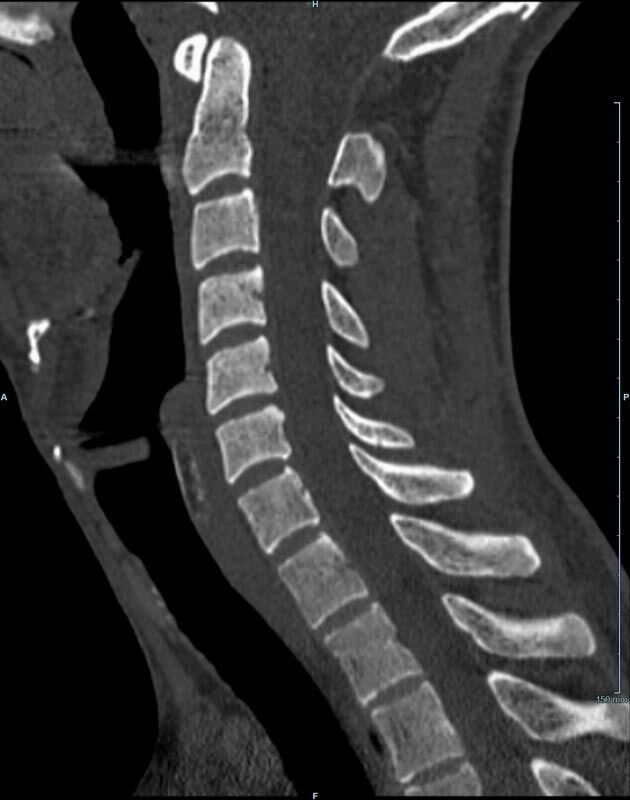

Wirbelsäule

• Darstellung von Frakturen, Tumoren und Bandscheibenveränderungen

Der Multislice-Scanner ermöglicht eine dem aktuellen Stand der Technik entsprechende, leitliniengerechte diagnostische Untersuchung sämtlicher Körperregionen. Darüber hinaus gestattet der neue Computertomograph auch eine für Arzt und Patient bequeme Durchführung CT-gestützter Interventionen wie z.B. Schmerztherapien der Wirbelsäule.

• besonders hochauflösende, strahlendosissparende Darstellung aller Skelettstrukturen